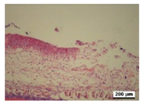

3.5. Histological Analysis